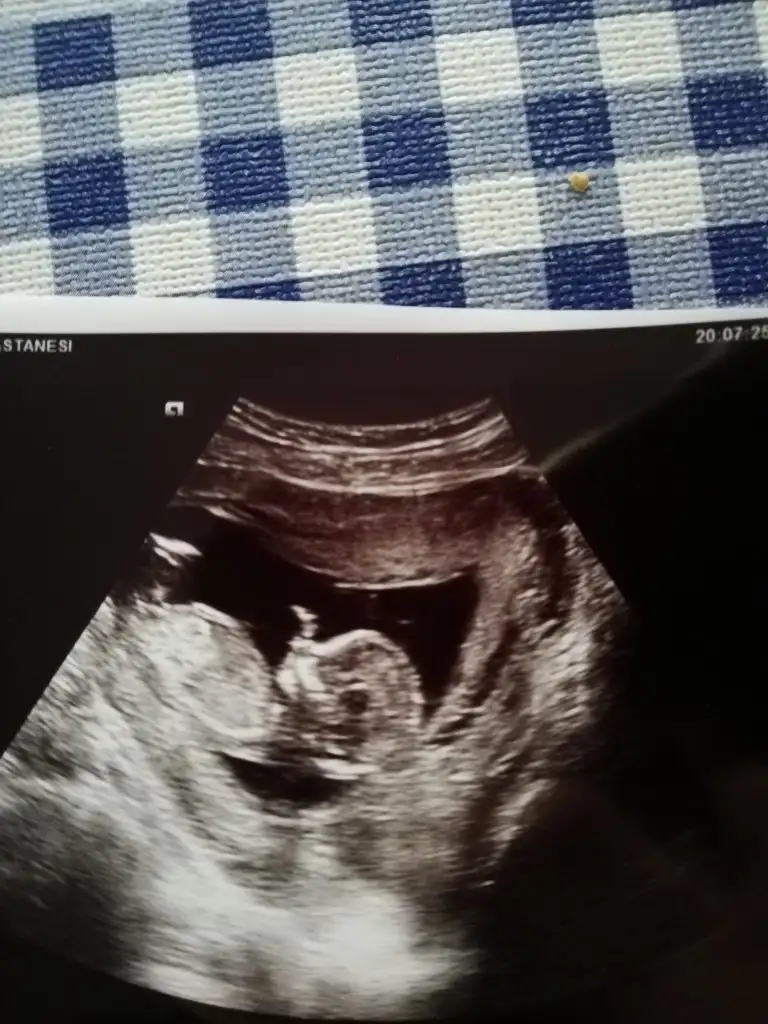

Kız gibi emin olamadım başka USG varsa paylaşın 11 12 13 haftalar olmalı

Doktorum da erkeğe benziyor dedi 12 haftalık tam orda :) ama kesin değil dedi. Bir kızım var hayırlısı ve sağlıklı sekılde birde oğlum olsun isterimErkek bu

Kız gıbı geldı banaIkra meyra banada bir yorum yapar mısınız

Nub 11 12. Haftalık belli oluyor çünküEvet regl dönem bakınca 8 hafta doktor 9+3 dedi.

Banada bakarmısınız bende 12 haftalık hamileyimKız gıbı geldı bana

bence kızınız olacak :)Bana da yardımcı olur musunuz cinsiyet tahmini olan var mı lütfen biraz net değil ama

net değil ama erkek olabilir :)Eki Görüntüle 2738465 bende çok merak ediyorum bana da yorum yapın lütfen ☺ 12+2 bu arada.